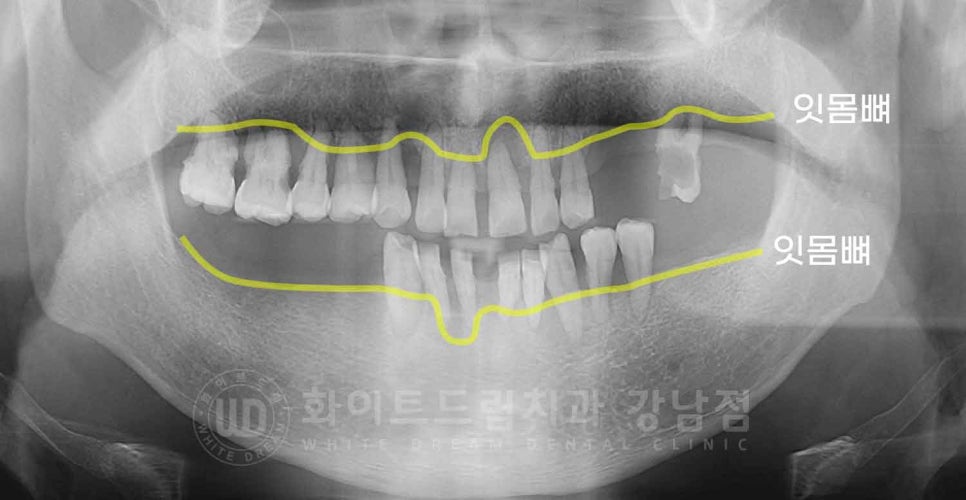

강남역 전악 임플란트, 치료 전 x-ray

환자분도 치주염이 심각하고, 흔들림이 심한 치아들이 많아 전체 발치 후 전악 임플란트 치료를 진행했습니다.

성공적인 임플란트 치료를 위해 발치 후 4개월간의 회복 기간을 가진 후 임플란트를 식립하는

'지연 시술'방법을 선택하여 진행했습니다.

이렇게 치주염이 심한 상태에서 임플란트를 식립하면,

임플란트의 고정력이 약해져 예후가 좋지 않을 확률이 높기 때문이죠.